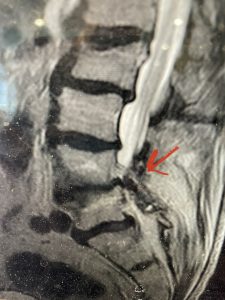

Epidural lipomatosis is a relatively rare condition where normally present fat in the epidural space is hypertrophied and can cause severe thecal sac compression. It is generally deposited more in the lateral and dorsal epidural space. This can be caused by long term steroid use and obesity, but also can be idiopathic. He had done well until more recently had developed low back pain with bilateral thigh pain and numbness. He had difficulty walking because of the pain. A new MRI (Fig 5) revealed that he had developed severe degeneration of the L1-2 segment above his prior decompression and fusion with a large extruded disc/osteophyte, right greater than left with severe thecal sac compression. He also had some residual T12-L3 residual epidural lipomatosis.

(Figs 5a): Sagittal (a) and axial (b) T2-weighted lumbar MRI demonstrating status post lumbar decompression and insitu fusion L2-5 now well decompressed (blue dash) with development of new (red arrow) severe stenosis and with superimposed right L1-2 disc herniation (blue arrow)

He had failed conservative treatment consisting of neurontin, physical therapy and epidural injections. He underwent revision laminectomy T12-L3 to decompress and explore prior fusion. He did have significant epidural fat encountered particularly at L1-2. The fat in epidural lipomatosis has a much more firm, globular texture. It takes a while to search within the fat, gently dissecting with a Penfield 4, to finally find the thecal sac! We encountered a large subligamentous extruded fragment lateral to the thecal sac on the right above the take off of the L2 nerve root. We removed any more residual fat at the L2-3 level and T12-L1 and decompressed the sac well. On exploration of the prior fusion it was fairly solid, but had some gaps at L2-3 fusion mass. Therefore we added a T12-L3 in situ fusion to augment those gaps and because we were at the thoracolumbar junction we extended fusion to T12. Post operatively he had relief of his leg pain.